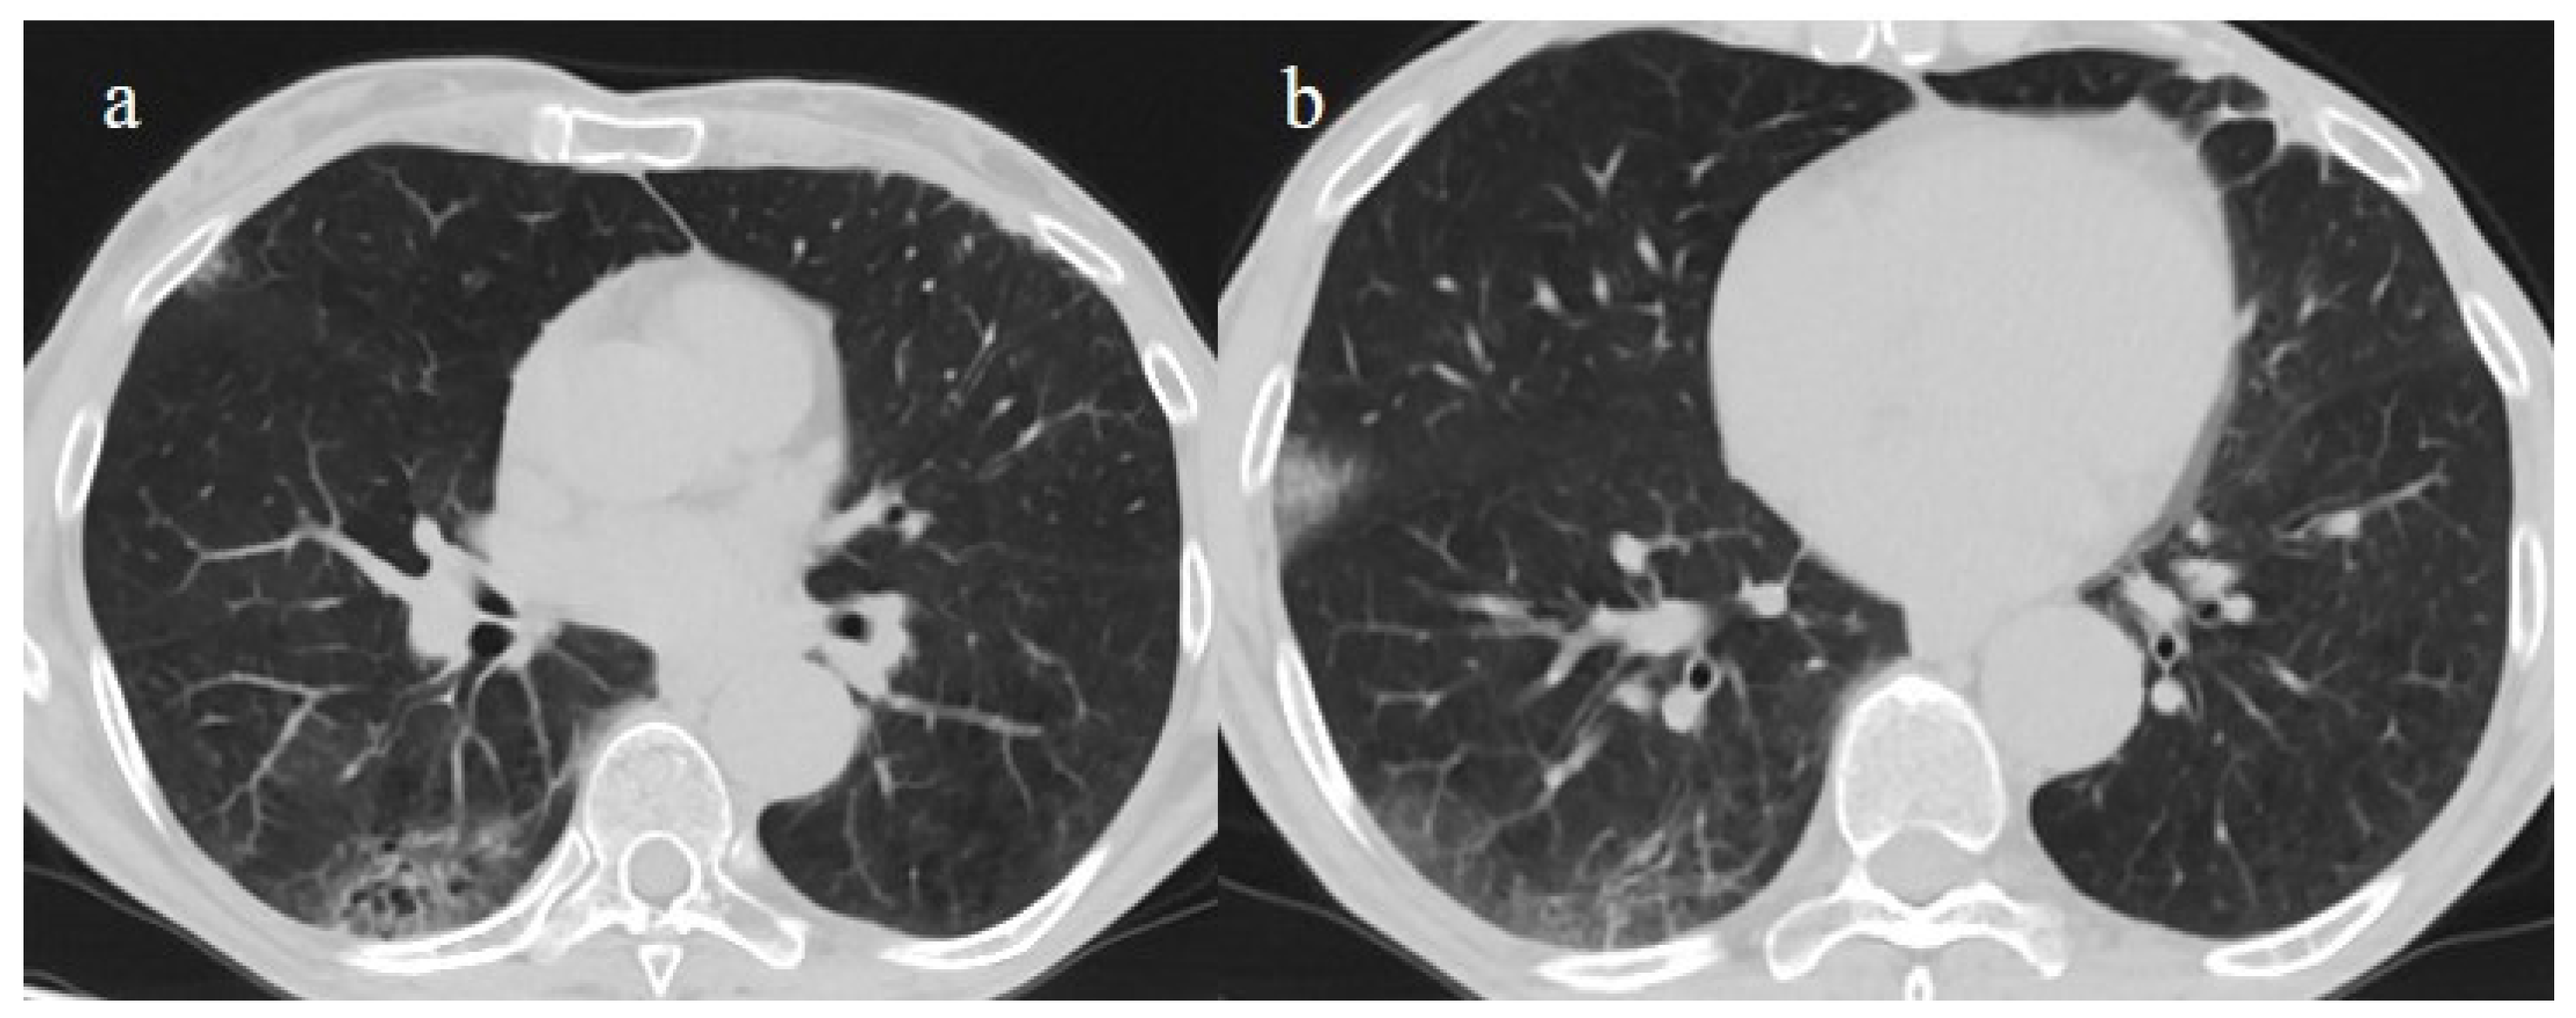

| Typical Appearance | GGOs with a crazy-paving pattern and consolidations in a peripheral and posterior or central-peripheral distribution; multilobar involvement; vascular enlargement, the halo and reversed halo sign; subpleural and parenchymal bands; and architectural distortion. They were predominant since the Delta wave. |

| Typical findings of interstitial pneumonia with peripheral or peripheral central distribution from the wild/type variant since Delta variant |

| Absence of pneumonia or atypical findings during the Omicron wave | |||

| Possible severe forms of COVID-19 pneumonia in breakthrough infections in the elderly and in patients with an immunosuppressive state | |||